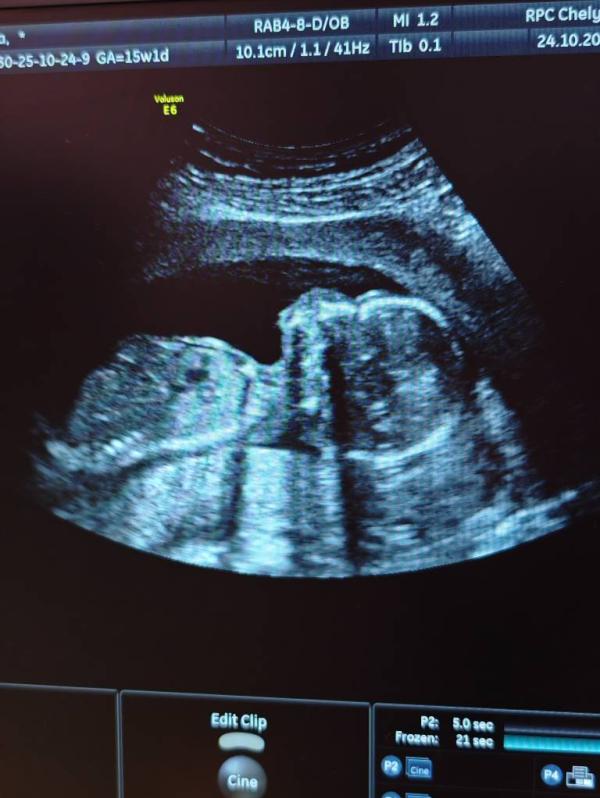

Позавчера 24.10 была на УЗИ в опц.

Гематом нет, отслоек нет, всё хорошо. Кровь, возможно, была от лопнувшего сосуда.

Срок поставил 15.5 (как по первому скринингу)

Плацента поднялась на 30мм, это низко, но уже не перекрывает зев. По задней стенке.

ШМ 35мм

Малыш весит 135г +/-20г

Чсс 150 уд/мин (на 1скр. было 170уд/мин)

Спинка носа 3.9 мм

Ктр не написал

Посмотрел все внутренние органы, ручки, ножки, глазки, всё измерил - всё в порядке

Пол определил уверенно, ждём мальчика🩵